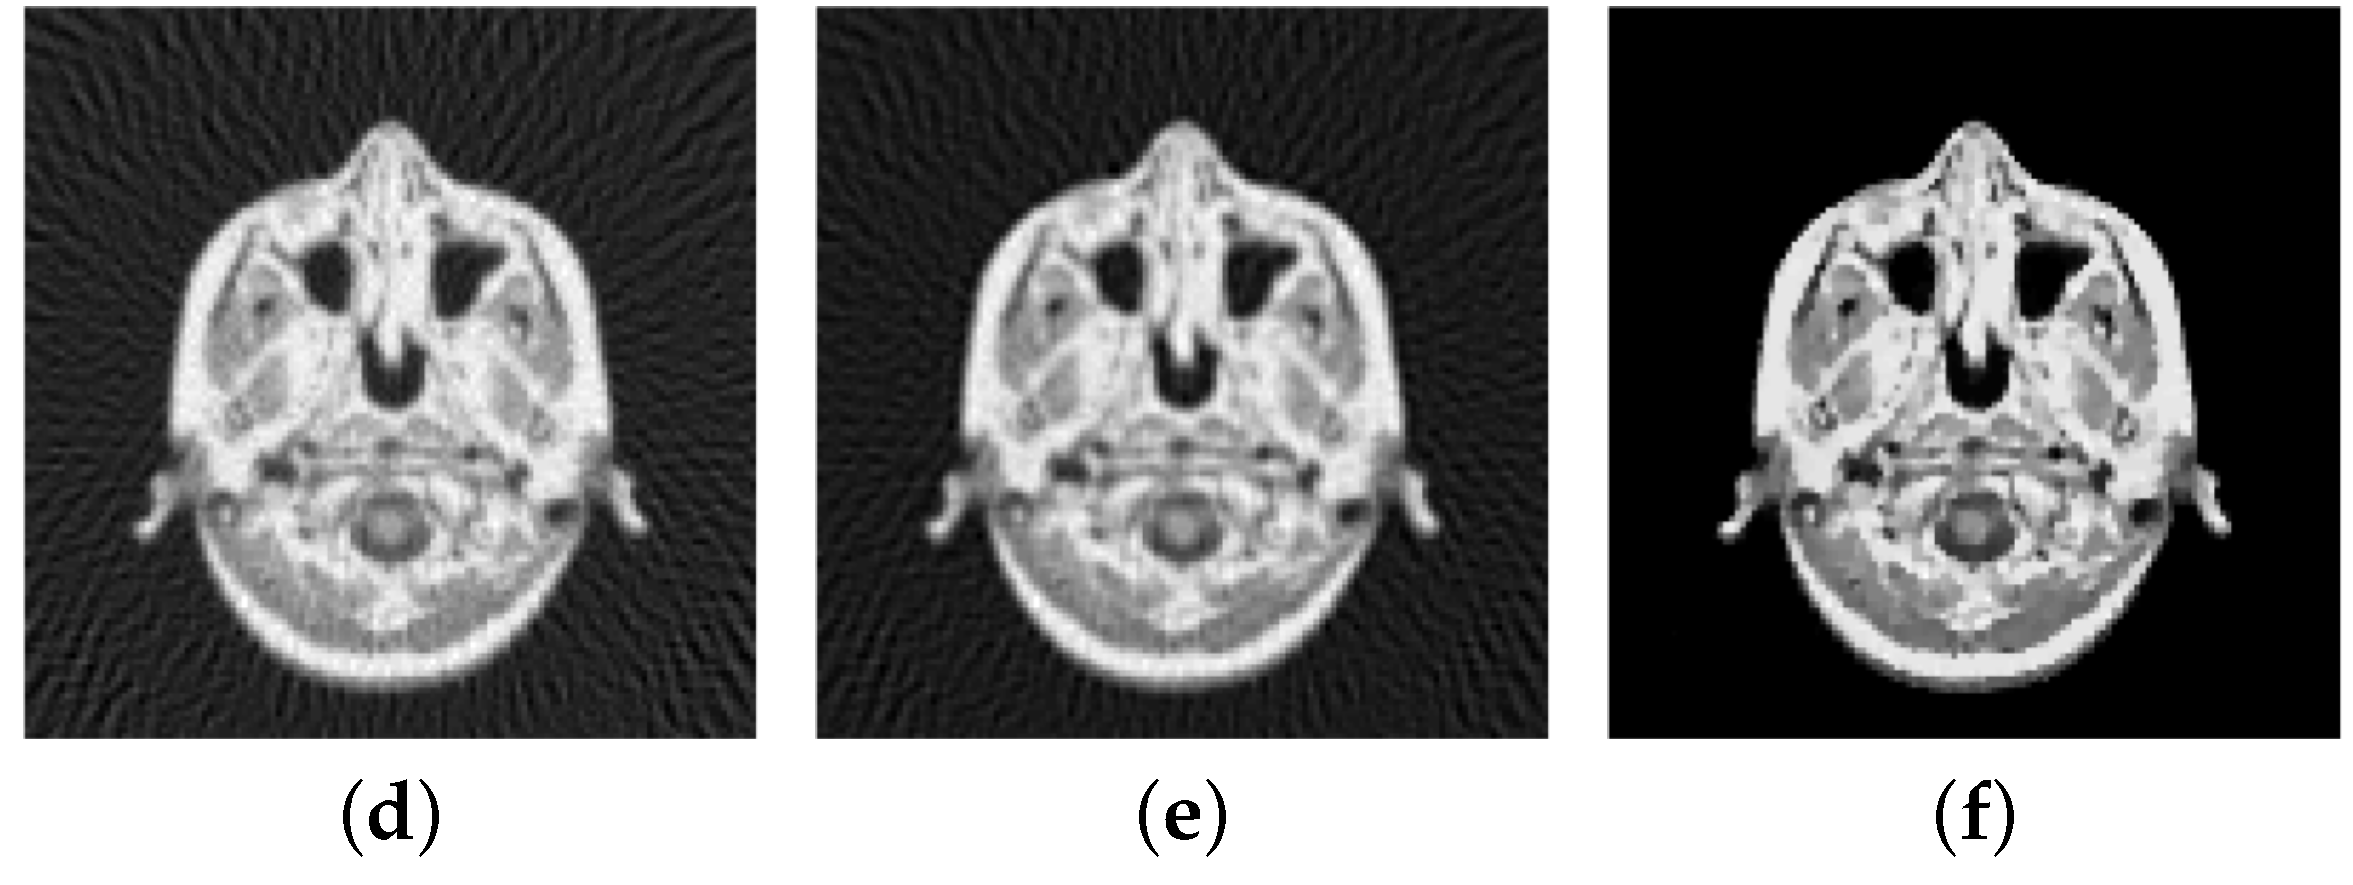

Figure 2.

Original images (a) Shepp-Logan phantom of size pixels (b) knee of size pixels (c) slice of a human brain of size pixels.

6.3.6. Reconstruction from Sampled Radon-Data

In computerized tomography instead of a Fourier-transform a Radon-transform is used in order to obtain a visual image from the measured physical data. Also here the data is obtained along radial lines. Here we consider the Shepp-Logan phantom, see Figure 14a, and a slice of a body, see Figure 15a. The sinogram in Figure 14a and Figure 15b are obtained by sampling along 30 and 60 radial lines, respectively, Note, that the sinogram is in general noisy. Here the data is corrupted by Gaussian white noise with standard deviation , whereby for the data of the Shepp-Logan phantom and for the data of the slice of the head. Using the inverse Radon-transform we obtain Figure 16a,b, which is obviously a suboptimal reconstruction. A more sophisticated approach utilizes the -TV model which yields the reconstruction depicted in Figure 16b,e, where we use the pAPS-algorithm and the proposed primal-dual algorithm with . However, since an image can be assumed to have non-negative values, we may incorporate a non-negativity constraint via the box-constrained -TV model yielding the result in Figure 16c,f, which is a much better reconstruction. Also here the parameter is automatically computed by the pAPS-algorithm and the non-negativity constraint is incorporated by setting in the semi-smooth Newton method. In order to compute the Radon-matrix in our experiments we used the FlexBox [52].

Figure 16.

Reconstruction from noisy data. (a) Inverse Radon-transform (PSNR: 29.08; MSSIM: 0.3906); (b) -TV (PSNR: 29.14; MSSIM: 0.4051); (c) Box-constrained -TV (PSNR: 33.31; MSSIM: 0.6128); (d) Inverse Radon-transform (PSNR: 31.75; MSSIM: 0.3699); (e) -TV (PSNR: 32.16; MSSIM: 0.3682); (f) Box-constrained -TV (PSNR: 36.08; MSSIM: 0.5856).